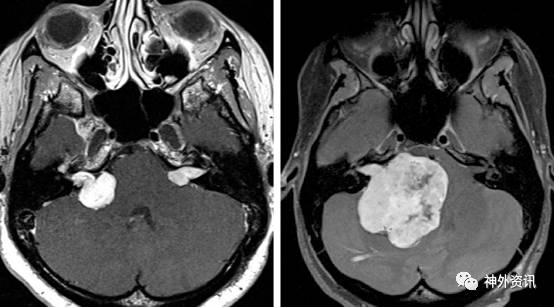

图1. 图示不同大小的VS,包括小型、中型和特大型VS。